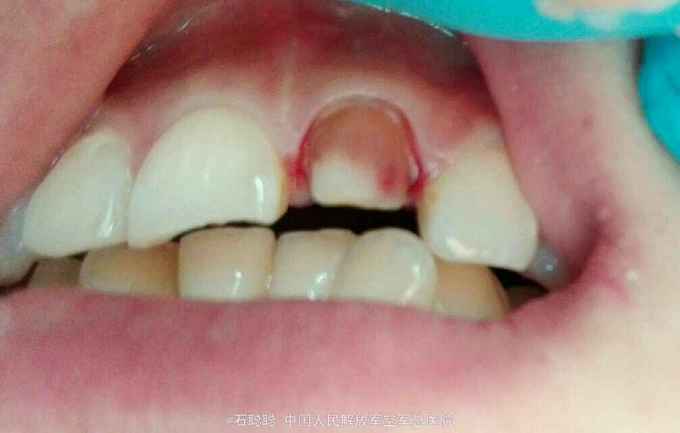

主诉:上前牙变色两年,要求改善牙齿颜色 现病史:诉两年前上前牙“变黑”,一年前该牙齿突发咬合不适,于外院行“根管治疗”,后无明显不适,自觉影响美观,来我科就诊 既往史:否认高血压、心脏病、糖尿病史,否认药物过敏史

检查:21牙体变色,切缘磨耗不均匀,舍面见牙色充填体完整在位,无松动,叩痛-,牙龈未见明显异常。 根尖片:21根管内高密度充填影像,恰填;12根尖远中见直径约3mm低密度透射影像 曲面断层:36、46残根,根尖低密度影

诊断:21牙体缺损 12慢性根尖周炎 治疗计划:21全冠修复 12根管治疗后全冠修复 处置:21备牙,取模,比色A3,制作临时冠,调合,粘接 一周后复诊: 检查:21临时冠完整在位,无松动,叩痛-,牙龈未见异常 处置:21去除临时冠,试戴银钯合金烤瓷冠,调合、磨光,粘接